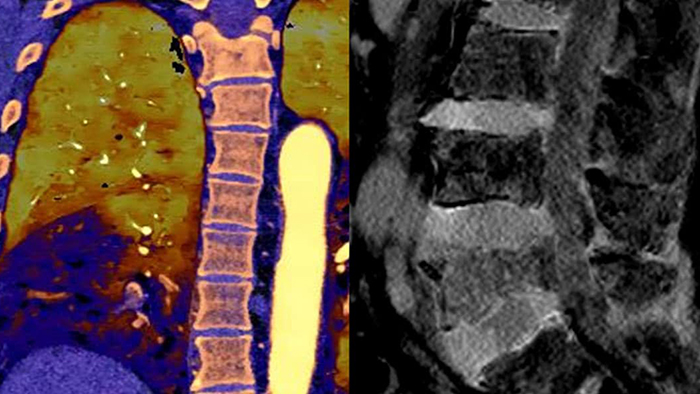

Unlike traditional CT images, spectral-detector CT images capture spectral information 100% of the time —without special planning or set-up. That means you can analyze the spectral data in any image retrospectively, using a variety of spectral viewing tools. You can, for example, adjust the monoenergetic level or get Zeffective maps.

Spectral detector simultaneously absorbs and differentiates high and low energy from a single polyenergetic X-ray beam. Spectral results are acquired within a single scan without the need for special modes.

Spectral CT helps me objectively differentiate contrast staining from hemorrhage, obviating the need for additional follow up scanning and prolonged patient observation, which can result in reduced costs and radiation exposure to patients.1,2